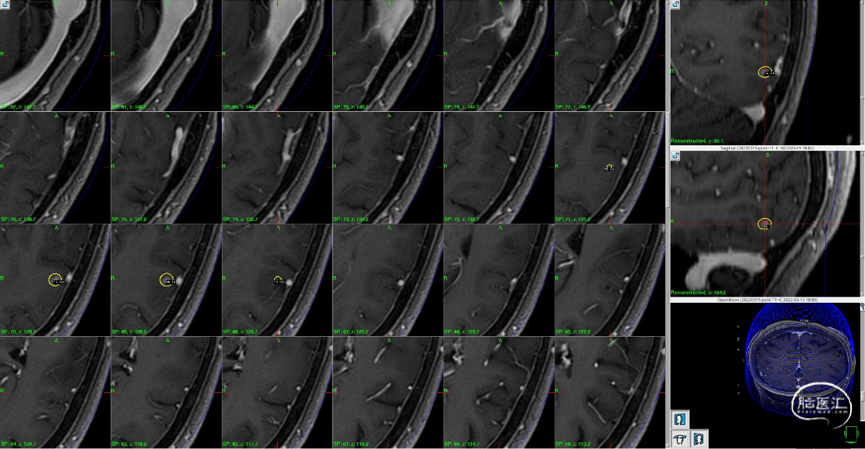

头颅MRI:显示左额、右侧侧脑室壁占位

1. 较大左侧额上回后部占位,向后挤压中央前回,增强后有明显强化。

2. 右侧侧脑室占位,增强后有明显强化。

磁共振MRI定位扫描(T1增强序列,1mm轴位连续断层薄扫)。

磁共振MRI定位扫描(T2平扫,2mm轴位连续断层+T1增强序列,1mm轴位连续断层薄扫)。

制定立体定向伽玛刀治疗计划(术中薄扫核磁扫面共发现4个病灶,除术前的2个病灶外,还发现2个小病灶);

1)左额囊性病灶治疗计划(分期治疗):边缘剂量11Gy(55%,中心20Gy),照射体积:16.563cm3。